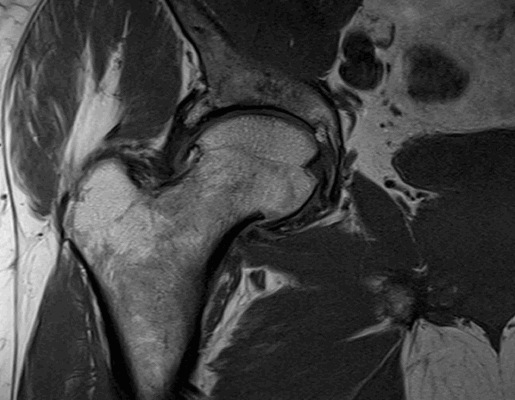

Импиджмент синдром на МР-фото

Магнитно-резонансное сканирование проводят для диагностики ряда патологических состояний. Что показывает МРТ тазобедренного сустава? На снимках визуализируются:

К механическому конфликту между бедренной головкой/шейкой и краем вертлужной впадины приводят одно- или двусторонние дефекты костей врожденного или приобретенного генеза. Видоизмененные компоненты сочленения вызывают дисфункцию конечности за счет соударения во время движения. Патологическое трение костей способствует разрастанию остеофитов на фоне постоянной травматизации вертлужной губы. Если своевременно не диагностировать заболевание и не начать лечение, последняя с течением времени разорвется., Хрящевая ткань сочленяющих костей будет разрушена. Подобный механический конфликт часто способствует формированию коксартроза и сопровождается прогрессирующим болевым синдромом.

МРТ тазобедренного сустава при феморо-ацетабулярном импинджмет-синдроме показывает возможные причины заболевания:

врожденные пороки развития;

осложнения после травм и оперативных вмешательств;

сопутствующий аваскулярный некроз головки бедра;

воспалительные процессы в синовиальной сумке;

остеохондропатию (болезнь Пертерса);

эпифизеолиз (перелом Салтера-Харриса);

атрофированные мышцы вокруг сочленения и пр.